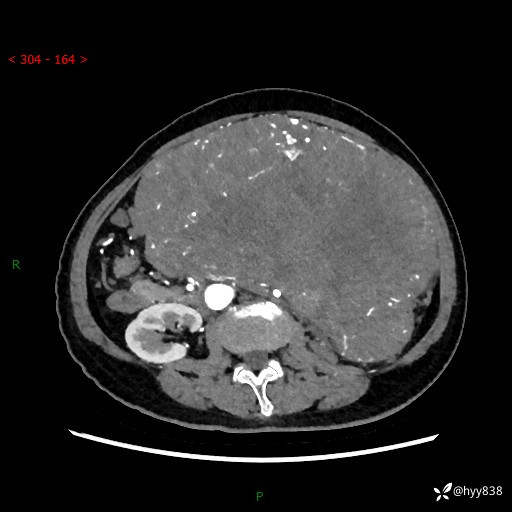

据说只有腹膜后,才能见到如此巨大的肿块---(有结果)

主诉:发现腹膜后占位1周

简要病史:患者1周前因头晕在当地第二人民医院检查发现左侧腹膜后区巨大富血供占位性病变,患者自诉腹部稍硬,无其他不适,无血尿,无腰痛等不适,患者为求进一步治疗来我院,门诊以“腹膜后占位性病变”收入我科。 起病以来,患者精神、饮食、睡眠可,大便正常,小便如上述,体力体重无明显改变。

临床诊断:腹膜后占位

腹部CT增强(动脉期+静脉期 ) ---平扫外院